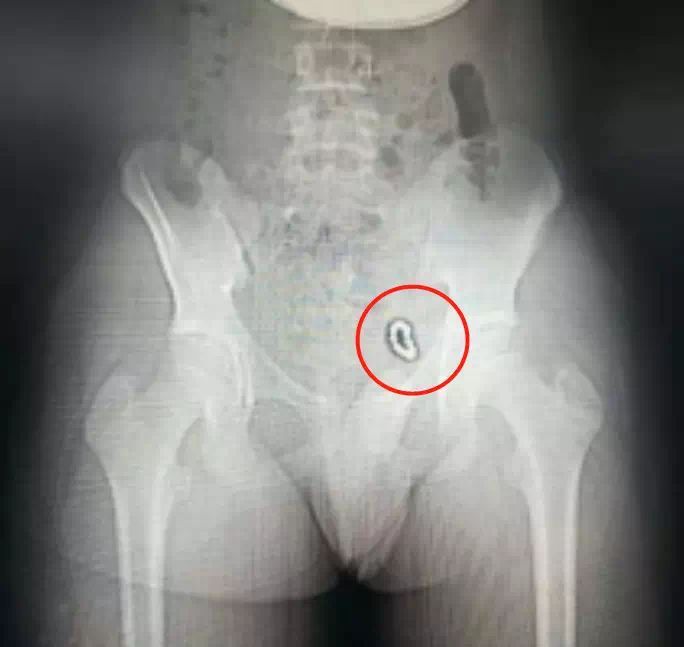

深圳13岁熊孩子

往“小鸡鸡”塞了14颗磁球

2018年11月,13岁的浩浩(化名)被爸妈带到深圳市儿童医院泌尿外科门诊。一周前,浩浩的下腹部开始隐隐作痛。尤其是跑步时,腹部沉沉的,痛得也更厉害。熬了几天后,就连小便也会痛。

医生耐心询问下才知道,原来浩浩向自己的“小鸡鸡”里塞过“巴克球”!而且塞了10多个,已经一年半以前的事了。

拍完X光片后,医生发现:浩浩下腹部左侧像是挂了一道环形“手串”,10多颗珠子紧紧连在一起,固定在膀胱左侧壁。尿检后发现,浩浩已经有了慢性膀胱炎,细菌正在尿液中滋长。

好在,医生经过手术

终于把这“巴克球”取出来